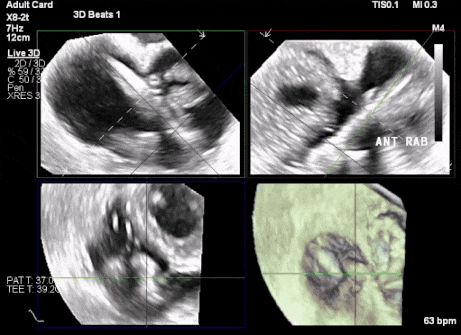

術(shù)中TEE成像困難,偽影干擾

術(shù)中TEE觀察夾持件的位置

術(shù)后超聲評估瓣膜穩(wěn)定性良好,無瓣周漏